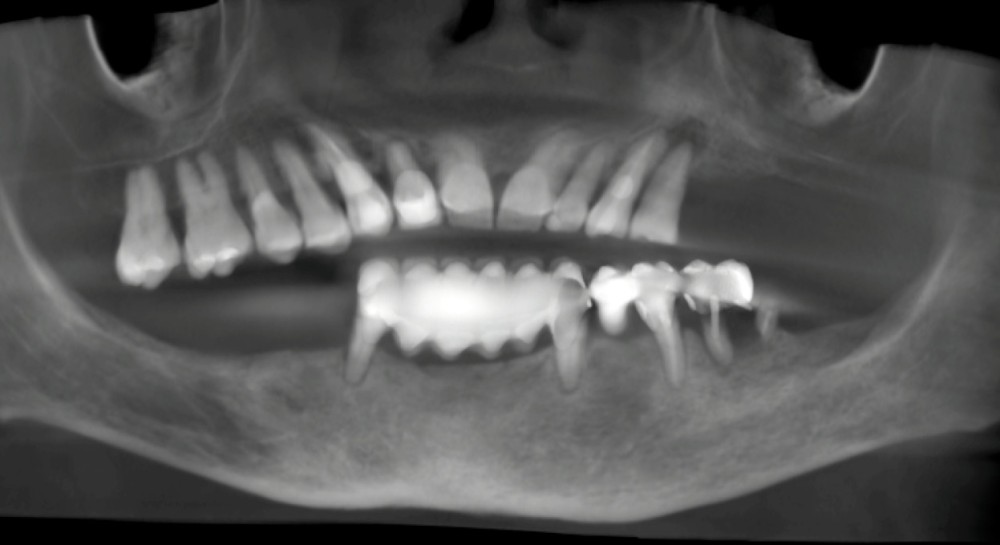

- cone beam pour l’analyse du volume osseux, l’étude des structures anatomiques et la planification implantaire tridimensionnelle (fig. 2) ;